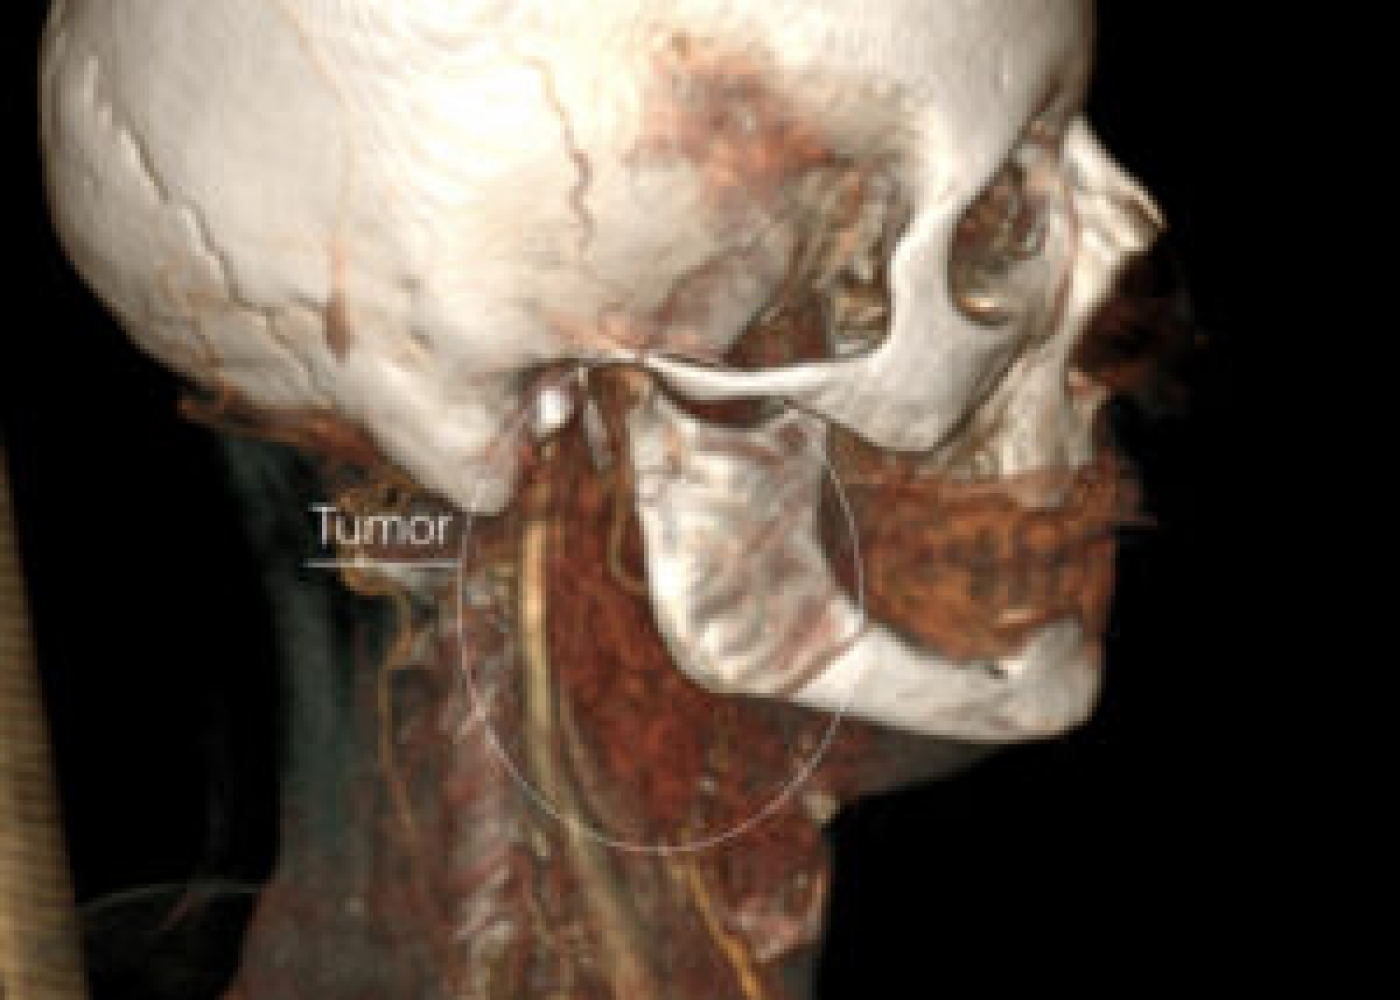

Պացիենտի խոսքով՝ գանգատներն ի հայտ են եկել մոտ 1,5 տարի առաջ և հաջորդիվ գոյացության չափերը զգալի մեծացել են: Հետազոտման ժամանակ աջից պարանոցի քնային եռանկյունում հայտնաբերվել է հստակ սահմաններով մոտ 4սմ տրամագծով անցավ գոյացություն:

Կլինիկոպարակլինիկական հետազոտությունների արդյունքում ախտորոշվել է քնային զարկերակի բիֆուրկացիայի անգիոմիոմատոզ համարտոմա աջից, որը ճնշում էր արտաքին քնային զարկերակը: